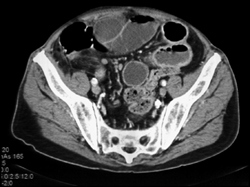

Diagnosis

Ischemic Bowel